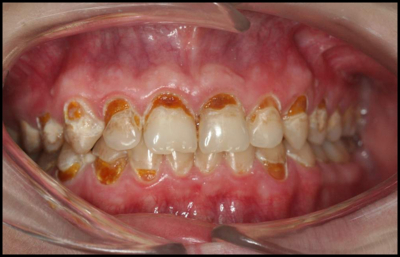

Your Enamel Is Under Constant Attack

Every beverage you consume creates an acid challenge in your mouth. A peer-reviewed study in the Journal of the American Dental Association tested 379 beverages available in the U.S. and found that 93% had a pH below 4.0 — well below the critical enamel dissolution threshold (Reddy et al., JADA, 2016; PMID: 26653863). A PRISMA-compliant systematic review of 19 studies confirmed that habitual consumption of carbonated acidic beverages causes structural disintegration and reduction of enamel's physical and mechanical properties (Cataldo et al., Nutrients, 2023; PMID: 37049624).

The demineralization process dissolves hydroxyapatite crystals — the mineral backbone of enamel — releasing calcium and phosphate ions. Once enamel is lost, it does not regenerate. This is not cosmetic damage. It is irreversible structural loss.

The Erosion Reality

What Your Favorite Drink Is Really Doing

Peer-reviewed research reveals the hidden damage of everyday beverages — and why EA Enamel Actives™ changes everything.

Soda & Cola (pH 2.4–2.7)

Phosphoric and citric acid cause ~24% calcium loss from enamel in a single prolonged exposure. Microhardness drops 16.7% on average.